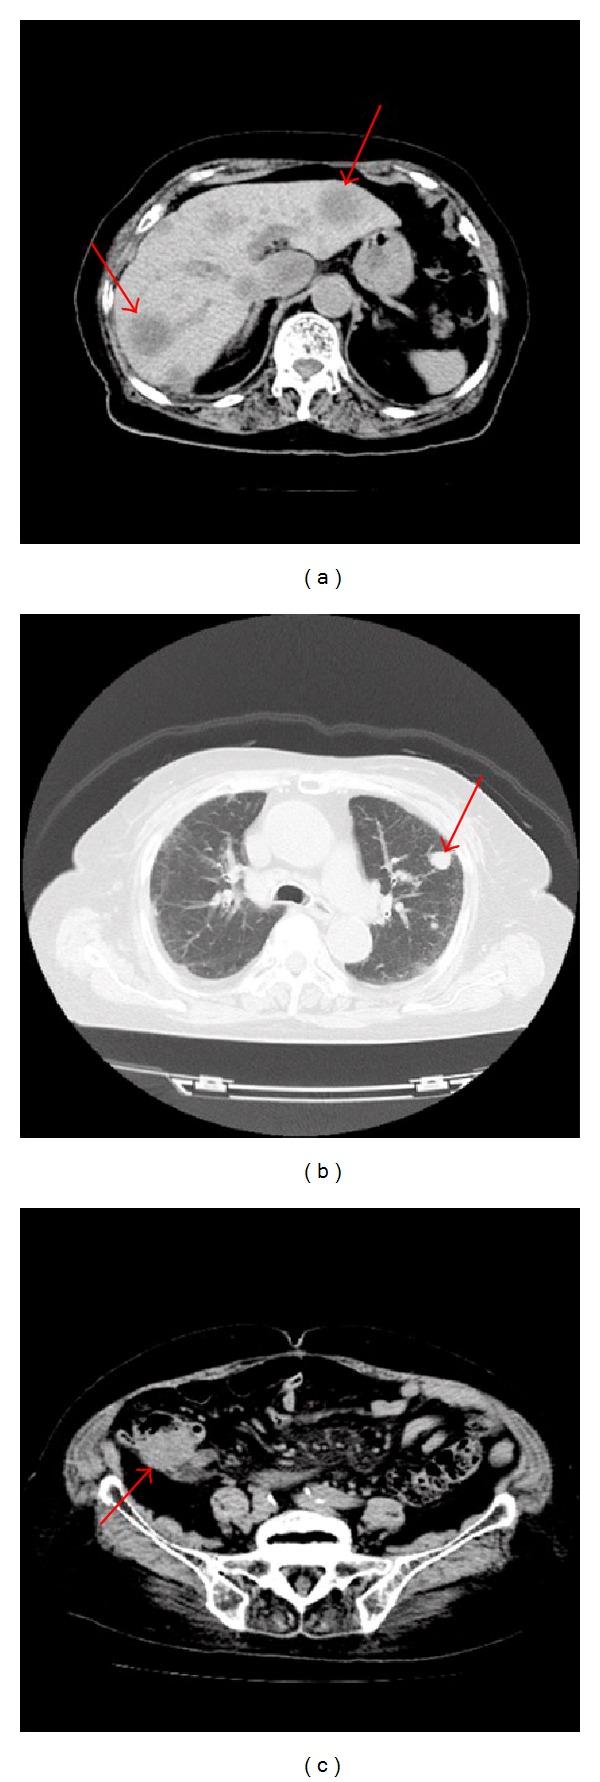

The purpose of this report is to present the findings in a case of squamous cell carcinoma (SCC) of the conjunctiva which was the initial sign of systemic cancers. A 94-year-old woman without known systemic diseases developed a mass in her right conjunctiva. She was referred to our hospital 5 months after the onset. She was diagnosed with conjunctival SCC by biopsy. Systemic CT before the surgery revealed multiple liver lesions, lung legions, and a large mass surrounding the appendix. The patient requested the surgery, and the main aim of the surgery was cosmesis. Histopathological examinations of the specimen led us to the final diagnosis as SCC. She did not receive any other therapy because of her age. As no other surgical procedures were undertaken, it is uncertain as to whether the conjunctival lesion was primary or secondary. Although, it is extremely rare that SCC of the conjunctiva is the initial sign of systemic cancers, careful systemic examinations to find other cancers should be made.